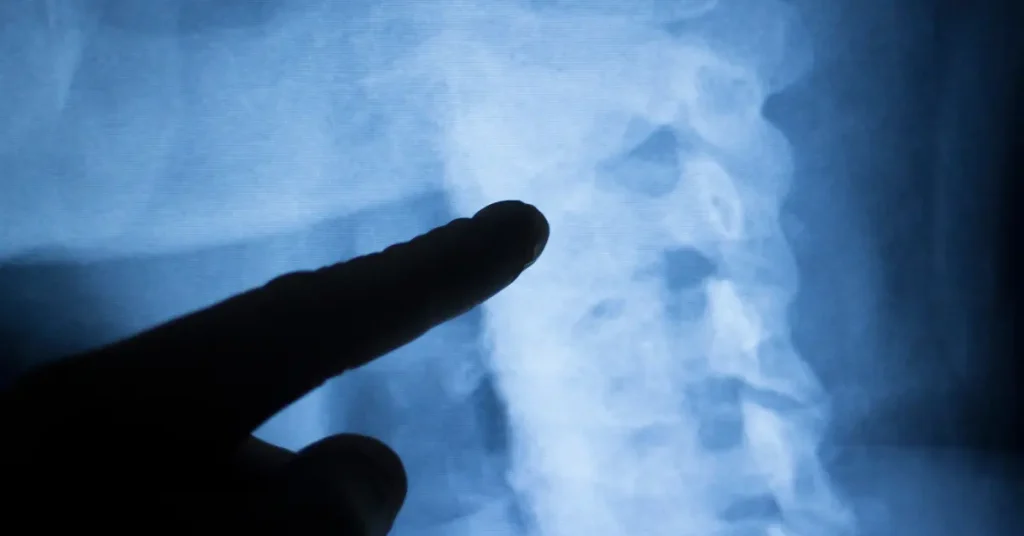

A central issue examined in the CHI pediatric hip surgery review is the Acetabular Index (AI), a radiological measurement used to assess hip development.

• International standard: Surgery is generally considered only when the AI exceeds two standard deviations from the mean.

• Audit findings: The Simon Thomas audit identified cases where surgery proceeded at substantially lower thresholds, including borderline measurements or non-specific clinical signs.

• Review goal: The CHI pediatric hip surgery review will apply internationally recognised Z-scores to determine whether non-surgical management would have been appropriate in specific cases.